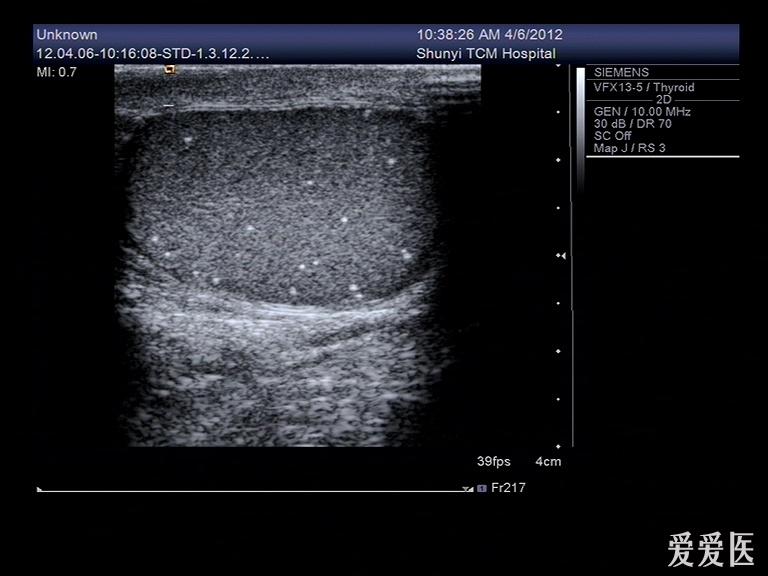

睾丸内点状强回声是什么东西?有图

前几天有个病人来检查,说睾丸疼,大小、形态都没什么变化,就是睾丸内有好多点状强回声,伴彗星尾征。请问这些东西是什么?钙化点?

典型的睾丸微石症

典型的睾丸微石症,有些人和结核有关系!